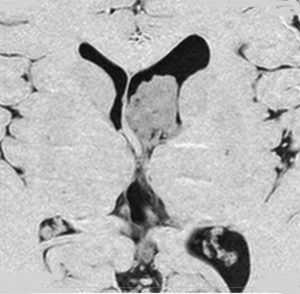

片側性水頭症

左尾状核から発生したものです。モンロー孔を閉塞して,片側性水頭症となっています。腫瘍がトリュフみたいにゴツゴツしているのも特徴です。

下のガドリニウム増強T1では,部分的に増強されます。

もちろん無症状ですが,年齢が若かったので全摘出しました。